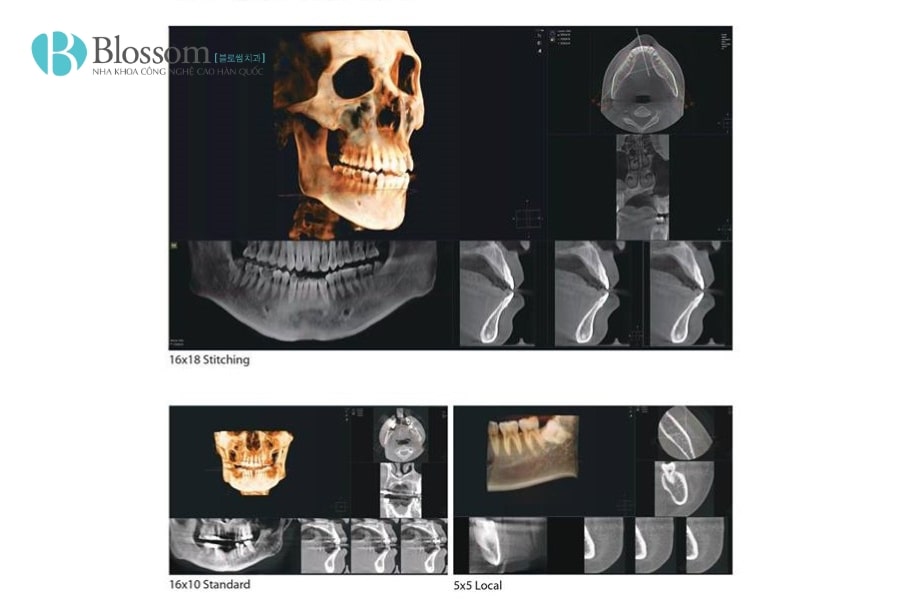

CT Cone Beam, viết tắt là CBCT (Cone Beam Computed Tomography), là kỹ thuật chụp hình ảnh 3D tiên tiến trong nha khoa. Máy sử dụng tia X hình nón quay 360 độ quanh đầu bệnh nhân để thu thập nhiều hình ảnh từ các góc khác nhau, sau đó tái tạo thành hình ảnh 3 chiều chi tiết của răng, xương hàm, mô mềm và ống thần kinh.

Khác với X-quang 2D truyền thống, CBCT cho phép quan sát toàn bộ cấu trúc hàm răng dưới nhiều góc độ, giúp bác sĩ đánh giá mật độ xương, vị trí dây thần kinh, xác định hướng đặt trụ Implant và lập kế hoạch điều trị chính xác. Quá trình chụp nhanh, không xâm lấn và ít tia bức xạ, mang lại sự an toàn và thoải mái cho bệnh nhân.

- Thời gian chụp nhanh: Chỉ mất 20–60 giây cho toàn bộ quá trình, tiết kiệm thời gian cho bác sĩ và bệnh nhân.

- Quan sát toàn bộ hàm răng trong một lần quét: Cung cấp cái nhìn tổng thể, giúp phát hiện các vấn đề tiềm ẩn mà các phương pháp khác có thể bỏ sót.